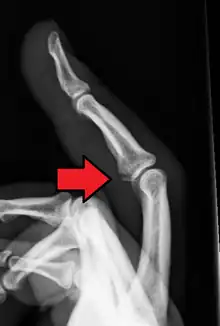

![]() | |

| Avulsion fracture of the proximal middle phalanx on the palm side | |